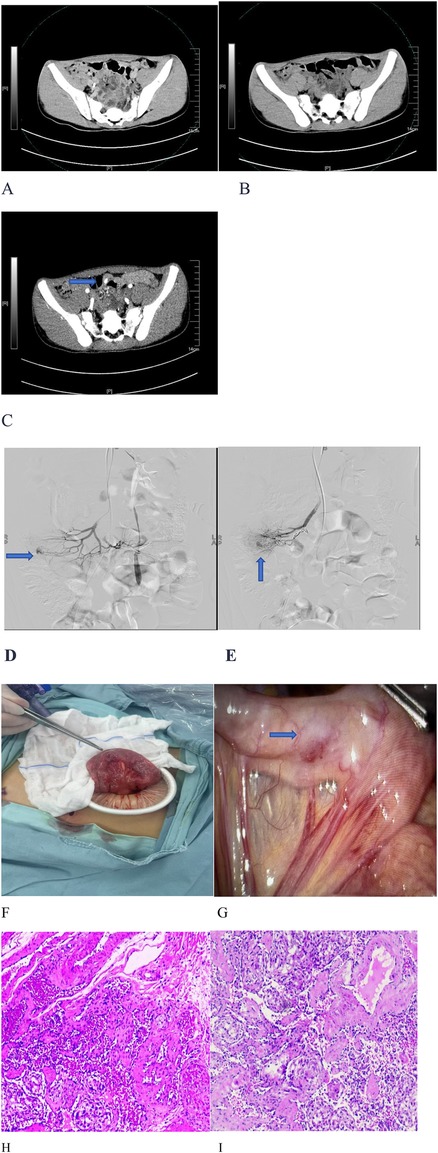

Abdominal contrast-enhanced CT revealed a hyperattenuating lesion in the small bowel of undetermined etiology (Figure 1C). Both a gastroscopy and a colonoscopy showed no abnormalities, indicating a small intestinal bleeding source. Scintigraphy for ectopic gastric mucosa was negative.

Figure 1. Imaging, angiography, surgery, and pathology of an ileal cavernous hemangioma. (A) No obvious lesion was identified on unenhanced phase imaging. (B) No abnormalities were observed in the portal venous phase. (C) A hyperattenuating lesion was detected during the arterial phase. (D,E) Superior mesenteric artery angiography revealed contrast extravasation from an ileojejunal artery branch, consistent with an active small bowel hemorrhage. (F,G) Laparoscopic exploration revealed a 1.5 cm × 1.5 cm mesenteric-based mass at the junction of the jejunum and ileum, which had a smooth and erythematous surface. (H,I) Hematoxylin-eosin staining demonstrated dilated congested sinusoidal spaces within the submucosa.

The Interventional Radiology Department recommended digital subtraction angiography (DSA) of the superior mesenteric artery. This examination showed contrast extravasation from the ileojejunal artery branches (Figures 1D,E), confirming an active small intestinal hemorrhage. A small intestinal hemangioma was initially suspected; however, after coil embolization of the ileojejunal artery branches, definitive hemostasis was not achieved.

Due to the child’s significant hemorrhage, the Pediatric Surgery Service recommended diagnostic and therapeutic laparoscopic exploration. Intraoperatively, a 1.5 cm × 1.5 cm mesenteric-based lesion with a smooth, erythematous surface was identified at the junction of jejunum and ileum (Figures 1F,G). The bleeding lesion was completely resected (Figures 1F,G). The final pathological examination confirmed it was a cavernous hemangioma (Figures 1H,I).

Computed tomography (SOMATOM Definition Flash, Siemens, Germany) revealed an arterial-phase enhancing lesion in the small intestine (Figures 1A–C). No abnormalities were found in gastroscopy and colonoscopy. DSA (Figures 1D,E) was conducted under ultrasound guidance, with the modified Seldinger technique used to puncture the right femoral artery and insert a catheter sheath.

After positioning the patient in a 30° right anterior oblique position (aligned with the prior CT scan for anatomical correlation), repeat angiography identified contrast extravasation from a jejunoileal artery branch in the mid-lower abdomen. Following superselection with a microguidewire-confirmed catheter, the branch was found to have aneurysmal changes with an active hemorrhage.

Laparoscopic exploration was performed to expose the ileocecal region. The exploration progressed sequentially from the ileocecal region. At the ileojejunal junction, a 1.5 cm × 1.5 cm mass with a smooth, erythematous surface was identified. Its base was attached to the mesentery. The mesenteric plane surrounding the mass was dissected toward its base using a harmonic scalpel. Multiple mesenteric vessels were visualized at the base. Consequently, conversion to laparotomy was performed for small bowel resection of the mass, followed by intestinal anastomosis.

A microscopic examination revealed twisted and dilated thin-walled vascular channels within the submucosa at the hemorrhagic site. The definitive pathological diagnosis was a cavernous hemangioma at the ileojejunal junction.